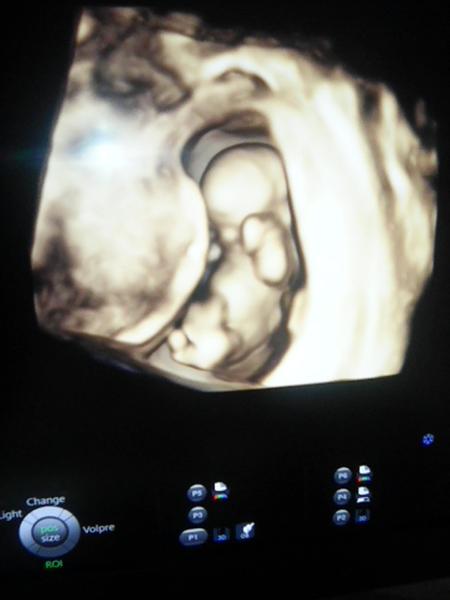

Aké pohlavie vidíte na tejto ultrazvukovej fotke?

Ahojte baby ,viete mi povedať ,či vidíte pohlavie na tejto fotke? Lekár mi nič ešte nevravel. Ďakujem za názory

Na tejto fotke NEVIDIET a neda sa povedat o ake pohlavie ide. Usg sa rozumiem, som Dr.

Inak ano, v 12 tyzdni sa da urcit pohlavie. U oboch deti mi v tomto tyzdni urcili. Ale urcite nie z tohto uhla ako je nasnimana tato foto.